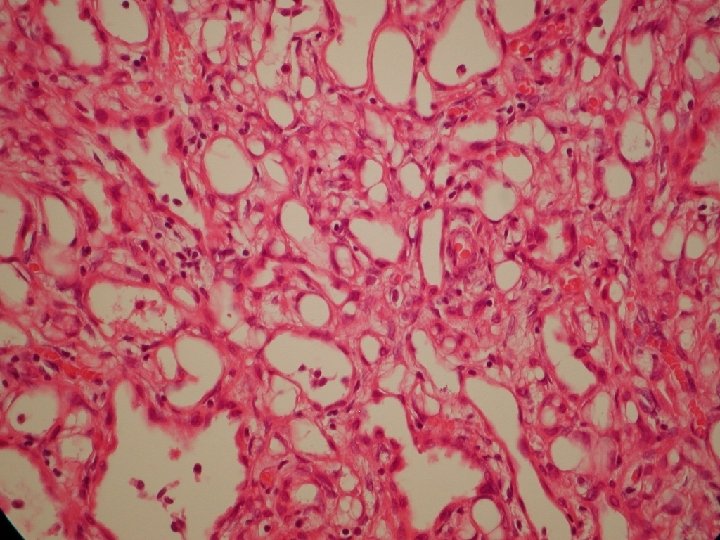

Popis a relevantné publikácie • Thread-like bridging strands: a morphologic feature present in all

Popis a relevantné publikácie • Thread-like bridging strands: a morphologic feature present in all adenomatoid tumors. Hes O, Perez-Montiel DM, Alvarado Cabrero I, Zamecnik M, Podhola M, Sulc M, Hora M, Mukensnabl P, Zalud R, Ondic O, Michal M. Ann Diagn Pathol. 2003 Oct; 7(5): 273 -7. • An immunohistochemical study of adenomatoid tumors of the uterus and fallopian tube. Terada T. Appl Immunohistochem Mol Morphol. 2012 Mar; 20(2): 173 -6. • Adenomatoid tumors of the female and male genital tracts: a clinicopathological and immunohistochemical study of 44 cases. Sangoi AR, Mc. Kenney JK, Schwartz EJ, Rouse RV, Longacre TA. Mod Pathol. 2009 Sep; 22(9): 1228 -35. doi: 10. 1038/modpathol. 2009. 90. Epub 2009 Jun 19.